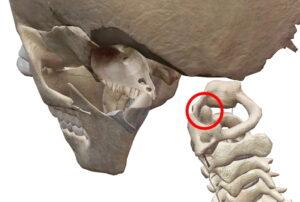

頭蓋の 縫合、上下顎骨と歯の釘植(ていしょく)がそれにあたります。

歯周病菌などに侵されたら歯は抜けますが、それ以外では当然動かない(動かせない)不動関節です。